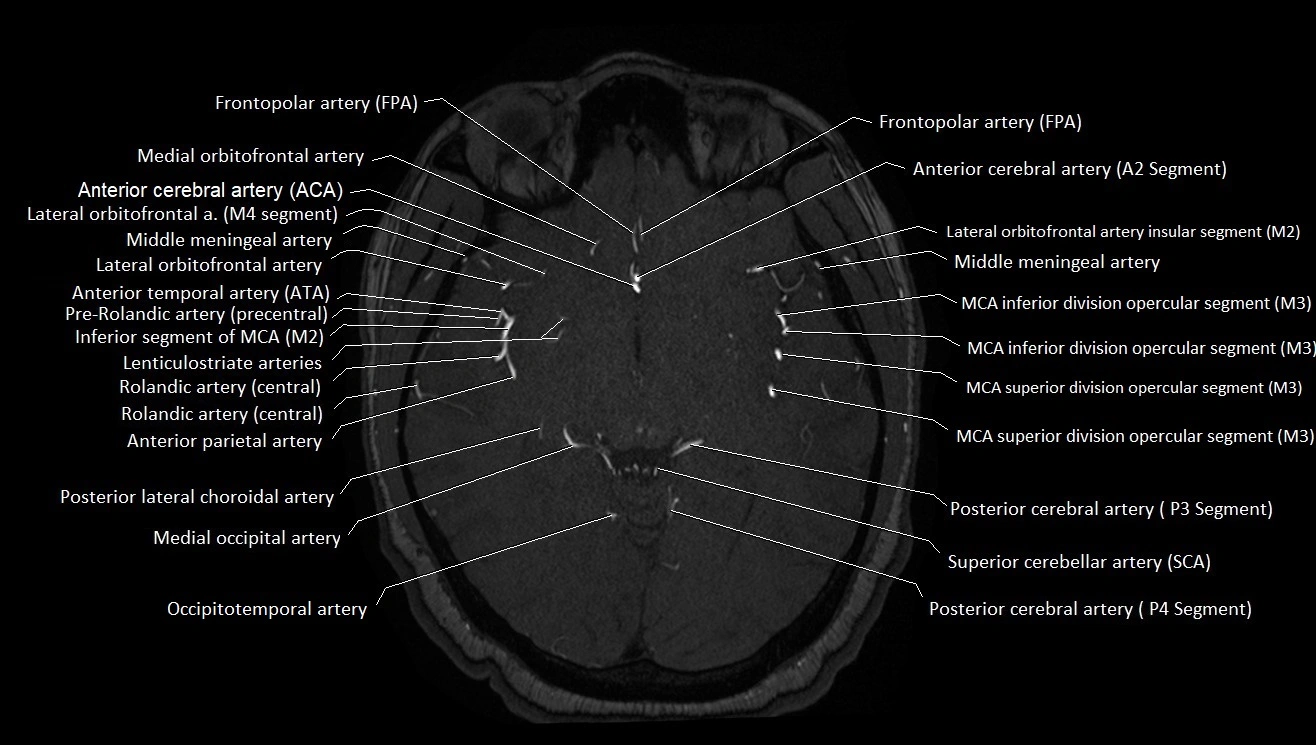

MRI images

image